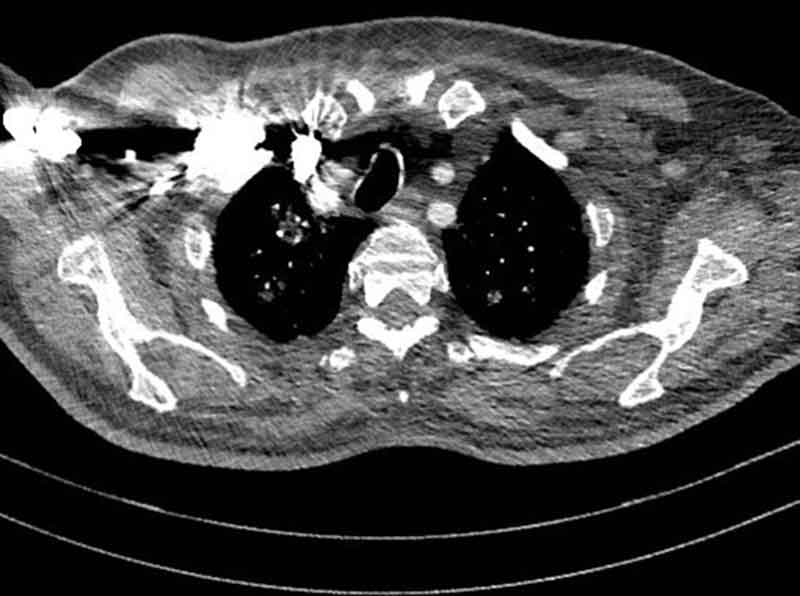

Contrast agent can help highlight certain features

injection or oral

ROI appears brighter

Dental Artifact

Contrast Artifact